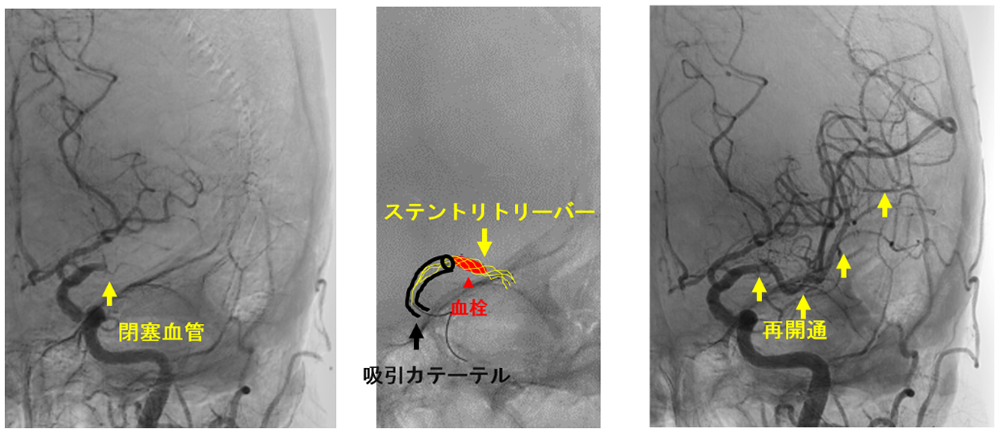

治療適応があると判断すれば、迅速にカテーテル室へ移ります。多くの場合、局所麻酔をした後、脚の付け根や腕の血管からカテーテルを挿入し、脳の動脈にカテーテルを進めます。閉塞している部分を確認し(写真左)、吸引カテーテルあるいはステントリトリーバーと呼ばれる器具を用いて血栓を回収します(写真中)。血栓が回収されると閉塞していた部分が再開通します(写真右)。手術時間は約1-2時間前後で、カテーテルが誘導しにくい場合や血栓が回収しにくい場合などは数時間かかることもあります。

良好な再開通(mTICI≧2b) 3は95.8%で達成しており(2024年の治療成績)、現在もより迅速かつ良好な再開通を目指し治療を行っています。直後から数日以内に症状が改善することもありますが、症状が残る場合はその後のリハビリテーションが必要です。